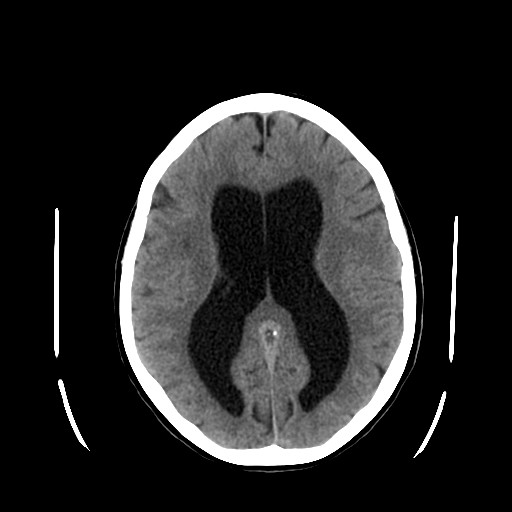

La hidrocefalia es una condición neurológica caracterizada por la acumulación anormal de líquido cefalorraquídeo (LCR) en los ventrículos del cerebro. Este exceso de líquido puede provocar un aumento de la presión intracraneal, daño cerebral y, si no se trata a tiempo, consecuencias graves para la salud. Aunque suele asociarse a la infancia, puede afectar a personas de todas las edades.

El diagnóstico de la hidrocefalia se basa en una combinación de evaluación clínica e imágenes cerebrales. Las técnicas más utilizadas incluyen:

-Tomografía computarizada (TC)

-Resonancia magnética (RM)